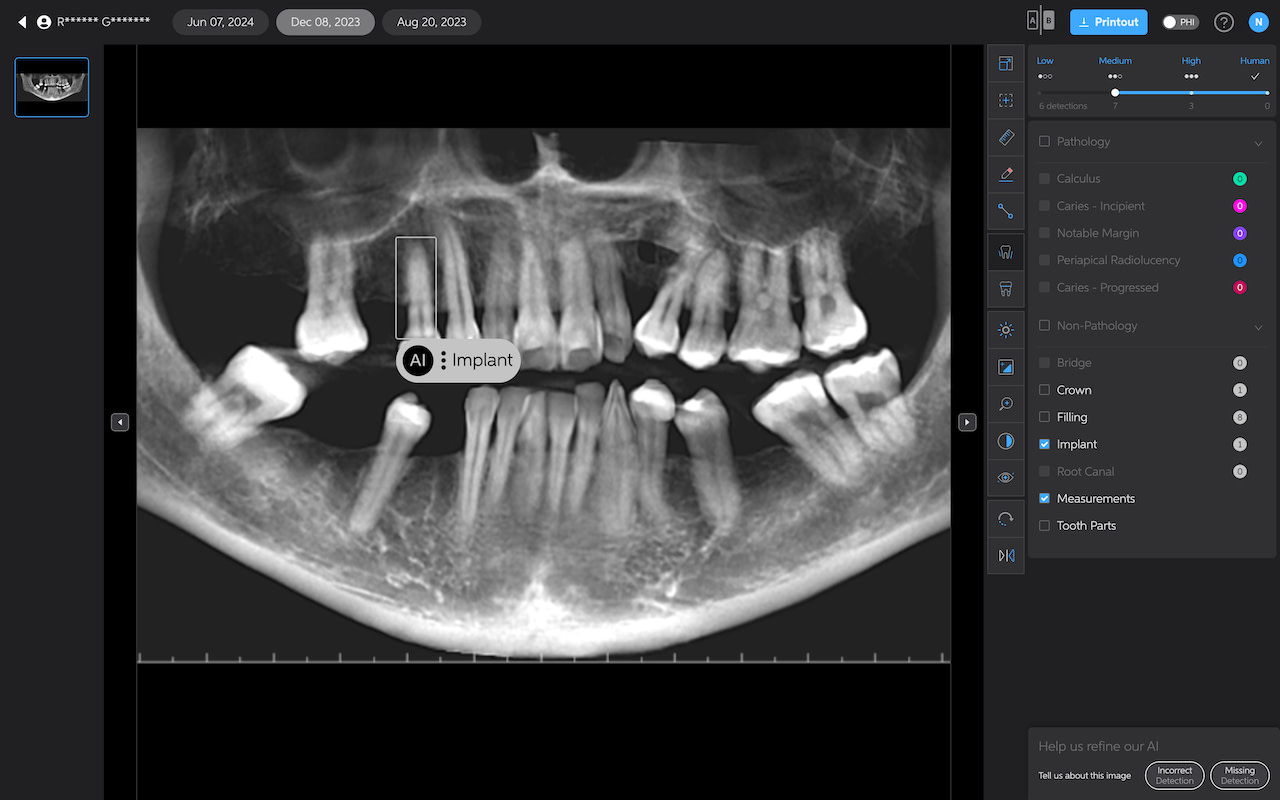

Pearl currently only analyzes 2D radiographs, including intraoral radiographs and OPGs. 3D X-ray analysis is under development and is scheduled for release later in 2025.

Here are some things I noticed AI missed or picked up incorrectly:

- It detects a ‘notable margin’ on an implant crown that is just the abutment-crown joint.

- Or calls a natural tooth an implant

- Or misses the apparent secondary decay under a PFM

- Seems to be less sensitive to widening of the PDL, rarely picking it up.

- It denoted leftover resin cement around a crown as calculus

- Does not seem to pick up resorbed roots

But overall, it is still impressive. Of course, AI does not have ‘bad days’, tiredness, or fatigue. It reports things the same way each time. It also gets better with time, one would hope.